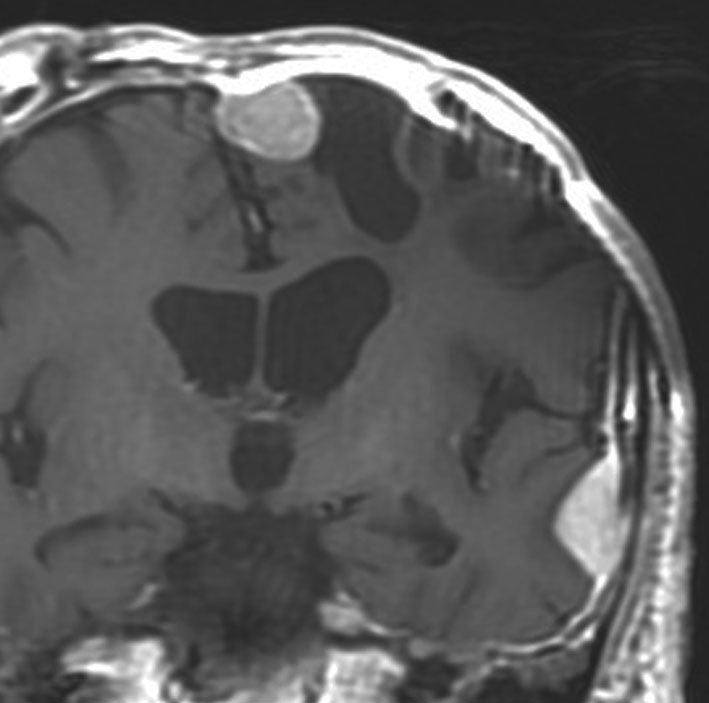

典型的な髄膜腫

この髄膜腫は中程度の大きさのものです。円蓋部髄膜種という最も多い最も手術の簡単なタイプです。麻痺や失語症やてんかんなどの症状はありません。とても美しくて若い女性の髄膜腫でしたが,子供に遺伝はしませんし,癌などと違ってタバコなどこれといった原因がなくて発生するものです。

MRIでの髄膜腫の見え方は撮影の仕方によっていろいろです。左からT1強調画像,T2強調画像,フレア画像といいます。腫瘍の横に小さく白い領域がありますが,これは脳の腫れた部分で脳浮腫といいます。髄膜腫があると周囲に脳浮腫が生じることがあります。

最も見やすいのが,ガドリニウム造影剤を注射して撮影するものです。一般的に髄膜腫は造影剤で白く映し出されます。この腫瘍は左脳側にあります。MRIの軸面という輪切りの写真では左右が逆になりますから注意してください。脳を下から見た図になっています。MRIはいろいろな方向から腫瘍を見ることができますが,右は冠状断という正面から見た図です。よく見ると腫瘍の上と下のはじっこに線状に糸を引いたように造影される部分があります。これをテールサイン(しっぽのサイン)といいます。腫瘍が硬膜に沿って延びている可能性があることを示しています。